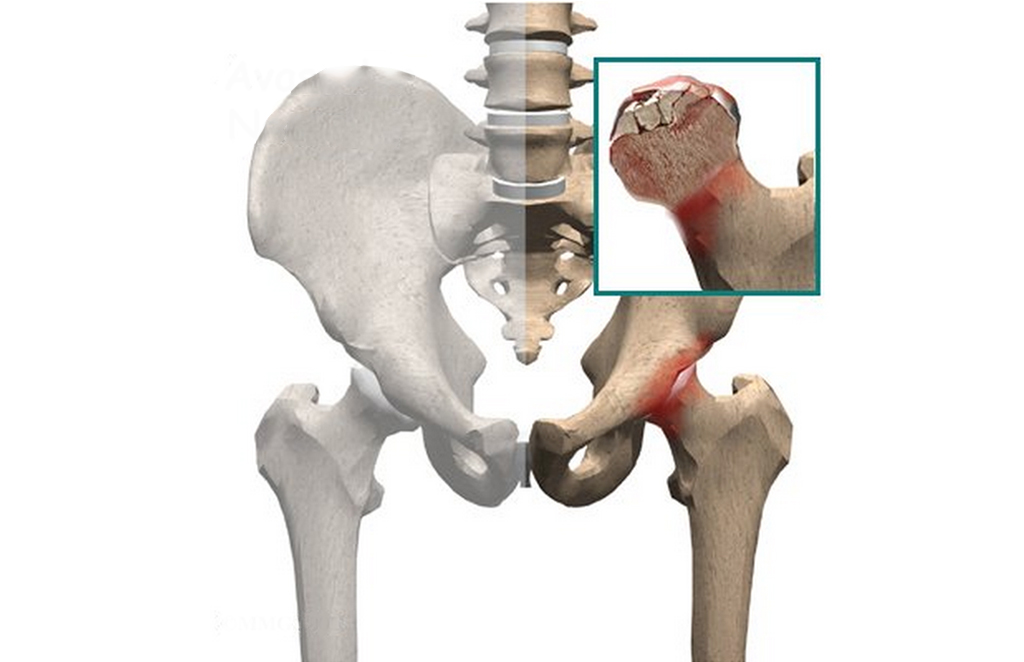

Avascular necrosis (AVN) is a prevalent kind of necrosis affecting the bones. The condition occurs when there is a loss of blood supply to the bone. An interruption to the blood supply to a bone causes it to collapse. An Injury or excessive use of alcohol or cortico-steroid can give rise to AVN. AVN of the femur head is one of the most common kinds of necrosis because the artery that gets injured is very narrow. In modern medicine, surgery is the only treatment for it but Ayurveda helps a lot as well. AyurHarsha an Ayurvedic hospital in Hyderabad is famous for Avascular Necrosis treatment with ayurvedic medicine and ayurvedic treatment.